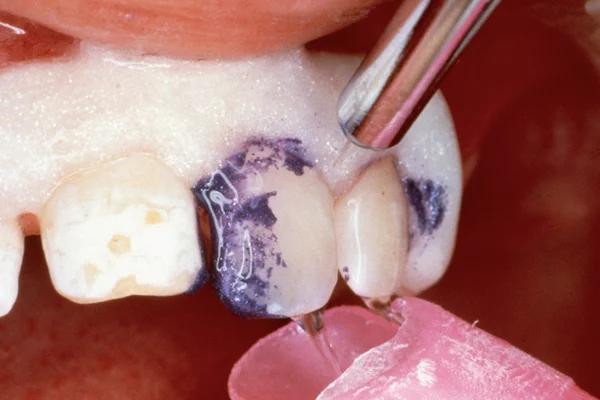

To improve isolation and soft tissue access, a retraction cord was placed before initiating the procedure (Fig. 2). The tooth was evaluated using a caries indicator dye (Kuraray Noritake Dental), helping to identify any remaining infected tissue beneath the dislodged composite (Fig. 3). Decay removal was completed with a diamond bur, and the enamel was bevelled using a starburst pattern to enhance aesthetic blending (Fig. 4). This preparation design was chosen for visual integration rather than bond strength enhancement.

4. Preparation of the lesion completed with diamond bur and starburst beveling pattern to enhance aesthetic blending.